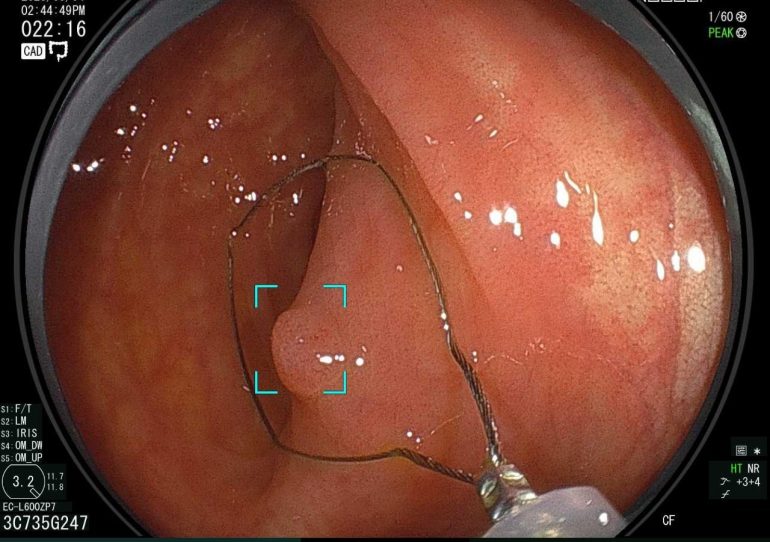

これまで当院で内視鏡検査を受けていただいた方々の症例紹介です。

当院では、下記の画像にあるような消化器疾患に対して質の高い内視鏡検査をご提供しています。

【大腸腺腫AI診断】

当院では、AIによる大腸がんの発見や大腸ポリープの鑑別を行うことができる最新の機器を導入しています。そのため、既存の内視鏡検査よりも質の高い検査をご提供させていただいております。

【日帰りの大腸ポリープ切除術】

こちらの症例のように、大腸カメラ検査中に大腸ポリープを発見した場合、その場で切除をすることが可能です。また、日帰りで大腸ポリープ切除術を行っているため、経済的にも時間的にも負担を少なく手術を受けていただけます。